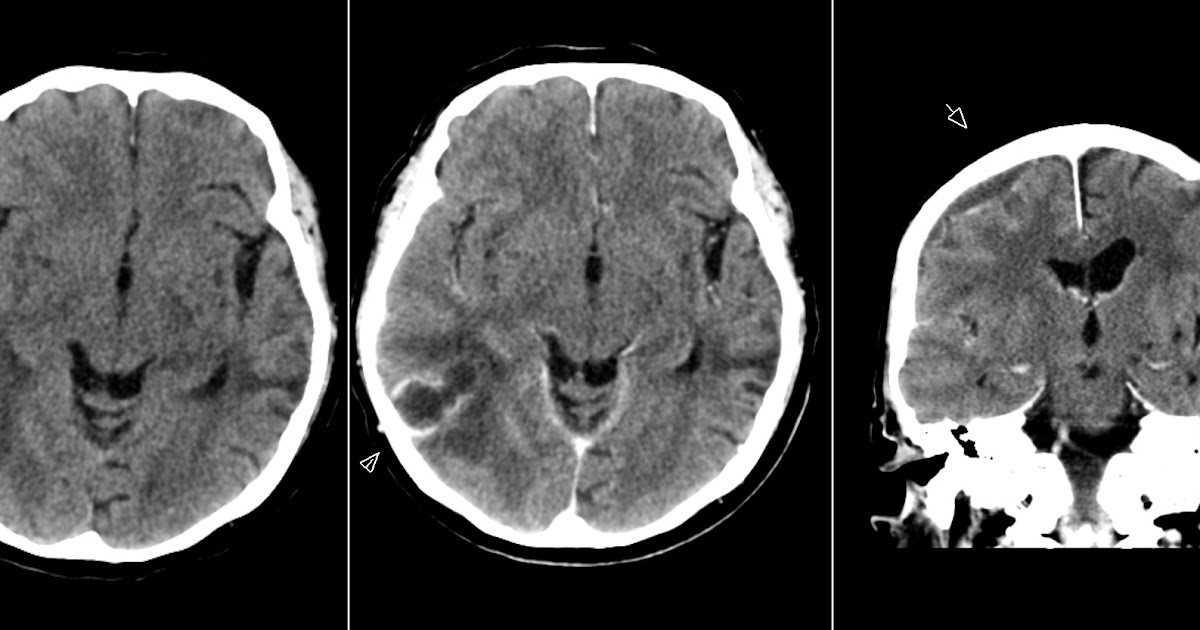

From radiologymri.blogspot.com

Radiology MRI Abscess and Subdural Empyema Abscess Vs Empyema these features are helpful in distinguishing a pulmonary abscess from an empyema (see empyema vs pulmonary abscess). In many patients with pneumonia,. empyema is defined by purulent fluid collection in the pleural space, which is most commonly caused by pneumonia. empyema is a condition that causes pus to develop in your pleural space, usually due to pneumonia.. Abscess Vs Empyema.

Radiology MRI Abscess and Subdural Empyema Abscess Vs Empyema a lung abscess involves the lung parenchyma, whereas an empyema involves the pleural space. the most reliable ct features for the differential diagnosis of lung abscess and empyema were wall characteristics,. In many patients with pneumonia,. Learn how to diagnose and. empyema is a condition that causes pus to develop in your pleural space, usually due to. Abscess Vs Empyema.